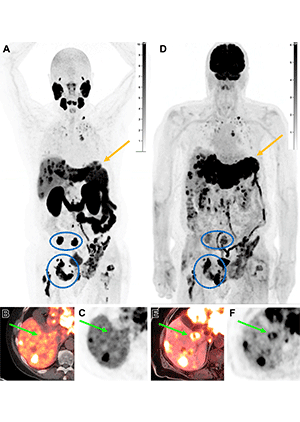

Intraindividual tumor heterogeneity in a 78-year-old man with progressing metastatic castration-resistant prostate cancer previously treated with hormonal therapy and docetaxel, who was referred for consideration of 177Lu–PSMA-617 therapy. 18F-DCFPyL PET/CT was performed to assess eligibility for treatment. (A–C) Coronal MIP (A), axial PET/CT (B), and axial PET (C) images show increased PSMA uptake in metastatic disease to the bones, liver, lungs, and supraclavicular nodes. However, several liver lesions are photopenic (arrow in B and C), concerning for PSMA-negative disease, which prompted evaluation with 18F–fluorodeoxyglucose (FDG) PET. (D–F) Coronal MIP (D), axial PET/MRI (E), and axial PET (F) images from 18F-FDG PET/MRI performed 1 month later show FDG uptake in the PSMA-negative liver lesions (arrow in E and F), in keeping with discordant FDG-avid PSMA-negative disease, concerning for more aggressive disease. Note the enlargement of the left hepatic lobe from quick progression of hypermetabolic metastases (arrow in A and D). The bone metastases show more intense uptake with PSMA than with FDG (blue circle and oval in A and D). On the basis of these findings, the patient was not considered a suitable candidate for RPT and was considered for second-line chemotherapy instead. https://pubs.rsna.org/doi/10.1148/rg.230097 ©RSNA 2023